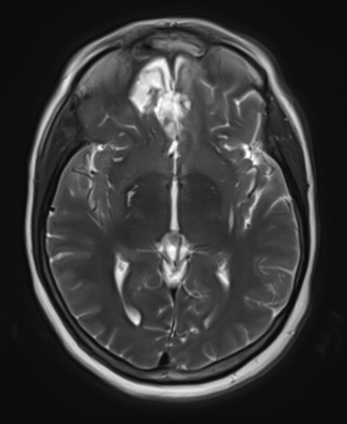

This is a 49-year-old otherwise healthy female who presented with bifrontal and retro-orbital headaches, behavioral changes, and forgetfulness. Symptoms have been progressively worsening over the past month. Her neurologic exam revealed a pronator drift, otherwise was unremarkable. MRI brain demonstrated a large extra-axial homogeneously enhancing mass of the anterior cranial fossa, resulting in significant mass effect and vasogenic edema (Figure 1a and 2a). Imaging was most consistent with a planum sphenoidale meningioma. She was referred to Dr. Xavier Gaudin for neurosurgical evaluation.

Figure 1a – Preoperative MRI demonstrating an extra-axial enhancing mass of the anterior cranial fossa.